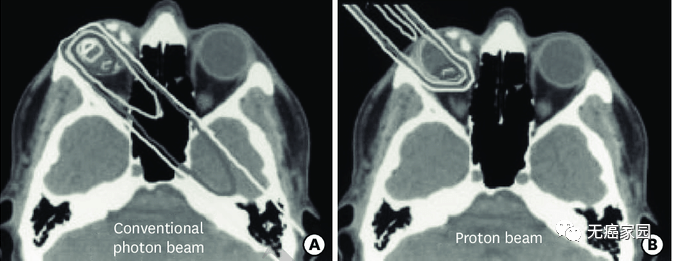

研究结果显示,与传统的光子放射疗法(EBRT)相比,PBRT具有物理优势。在下图的典型病例示意图中,传统光子治疗在眼内靠近肿瘤的部位剂量较大,而且后眼眶和脑内肿瘤远端的剂量也明显高于质子治疗。

研究表明,在维持眼球的情况下,质子束具有比常规光子束更低的辐射剂量,而且最终可以使眼功能最大化。